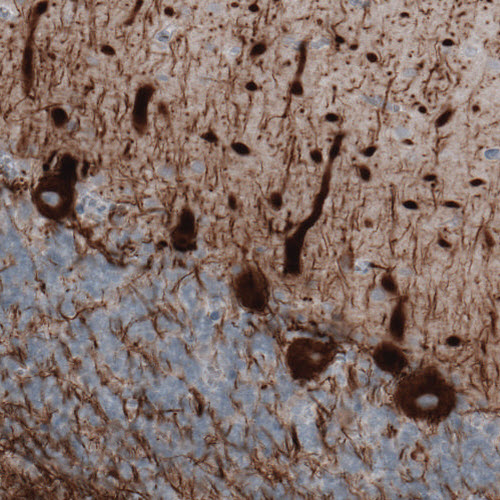

Immunohistochemical staining of rat cerebral cortex shows strong immunoreactivity in neuronal processes.